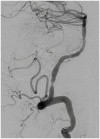

In this review article, we summarized the current advances in rescue management for reperfusion therapy of acute ischemic stroke from large vessel occlusion due to underlying intracranial atherosclerotic stenosis (ICAS). It is estimated that 24-47% of patients with acute vertebrobasilar artery occlusion have underlying ICAS and superimposed in situ thrombosis. These patients have been found to have longer procedure times, lower recanalization rates, higher rates of reocclusion and lower rates of favorable outcomes than patients with embolic occlusion. Here, we discuss the most recent literature regarding the use of glycoprotein IIb/IIIa inhibitors, angioplasty alone, or angioplasty with stenting for rescue therapy in the setting of failed recanalization or instant/imminent reocclusion during thrombectomy. We also present a case of rescue therapy post intravenous tPA and thrombectomy with intra-arterial tirofiban and balloon angioplasty followed by oral dual antiplatelet therapy in a patient with dominant vertebral artery occlusion due to ICAS. Based on the available literature data, we conclude that glycoprotein IIb/IIIa is a reasonably safe and effective rescue therapy for patients who have had a failed thrombectomy or have residual severe intracranial stenosis. Balloon angioplasty and/or stenting may be helpful as a rescue treatment for patients who have had a failed thrombectomy or are at risk of reocclusion. The effectiveness of immediate stenting for residual stenosis after successful thrombectomy is still uncertain. Rescue therapy does not appear to increase the risk of sICH. Randomized controlled trials are warranted to prove the efficacy of rescue therapy.